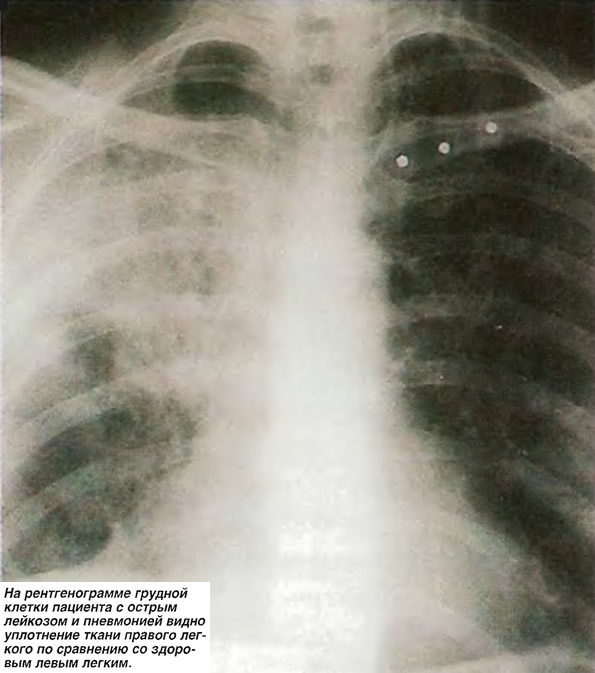

Рентгенологические изображения и синдромы патологии легких